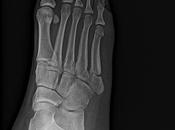

Fractura por múltiples fragmentos a nivel de cabeza de falange distal del 5to...

RADIOGRAFIAS AP Y LATERAL DE 5TO DEDO Hallazgos: -En lo observado de metacarpos, sin evidencia de lesiones blásticas, líticas o perdidas de la contigüidad. Leer el resto